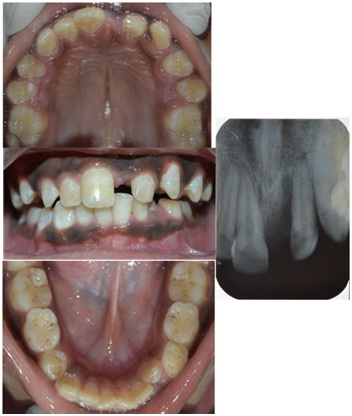

An 11-year-old boy accompanied by his parents reported to the Department of Pedodontics and Preventive Dentistry, with the chief complaint of tooth lost in the upper front region in a road accident. The parents reported the history of avulsion of left central incisor two years back. Intraoral examination revealed a mixed dentition, maxillary arch was oval in shape and maxillary right and left second premolars were buccally erupting. Mesio-buccal rotations were seen in maxillary second premolars and left maxillary canine. Class I molar relation on both sides and a 3 mm space loss in relation to 21. It was confirmed with IOPA [Table/Fig-8]. The case was undertaken for space regaining with modified 2 by 3 fixed appliances, followed by fixed functional space maintainer.

After two months follow-up, it was observed that the desirable space was gained, as showed in the IOPA [Table/Fig-10].

The brackets were debonded, an alginate impression was made bands were stabilized in impression and working cast was prepared. A modified Nance appliance was fabricated and replaced the lost tooth with an acrylic tooth [Table/Fig-11].